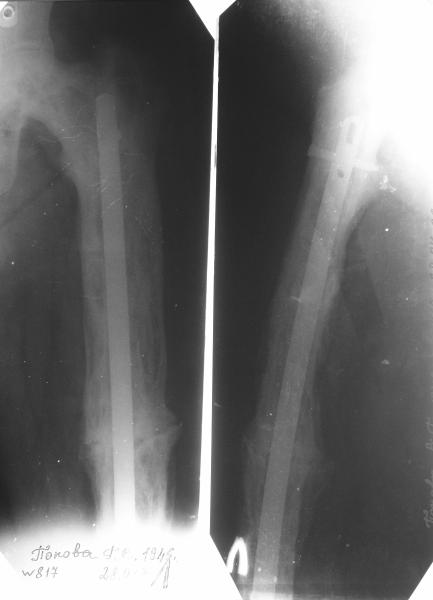

Re: перелом бедра на фоне болезни Педжета

Еще один пример. Пациентка с юга России, прислала рентгенограммы через год. На сегодня прошло 2 г. 8 мес. после операции. Несмотря на не очень убедительный процесс сращения, пациентка ходит. Учитывая остеопороз при Педжете, решили, что динамизировать вообще не нужно.